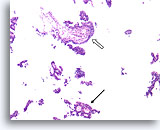

Proliferatieve ductale laesie, Papillair neoplasma vs fibroadenoom, Borst FNA, Directe uitstrijk.

De cellulaire details worden gedeeltelijk geblokkeerd door bloed, maar een grote groep proliferatieve ductale cellen kunnen aan de linkerkant worden waargenomen. Aan de rechterkant bevindt zich een stromaal fragment met ronde randen.

Proliferatieve ductale laesie, Papillair neoplasma vs fibroadenoom, Borst FNA, Directe uitstrijk.

De cellulaire details worden gedeeltelijk geblokkeerd door bloed, maar een grote groep proliferatieve ductale cellen kunnen aan de linkerkant worden waargenomen. Aan de rechterkant bevindt zich een stromaal fragment met ronde randen.